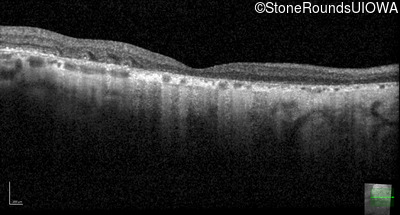

Optical Coherence Tomography - Left - 20/200

Exemplar / OCT Stack